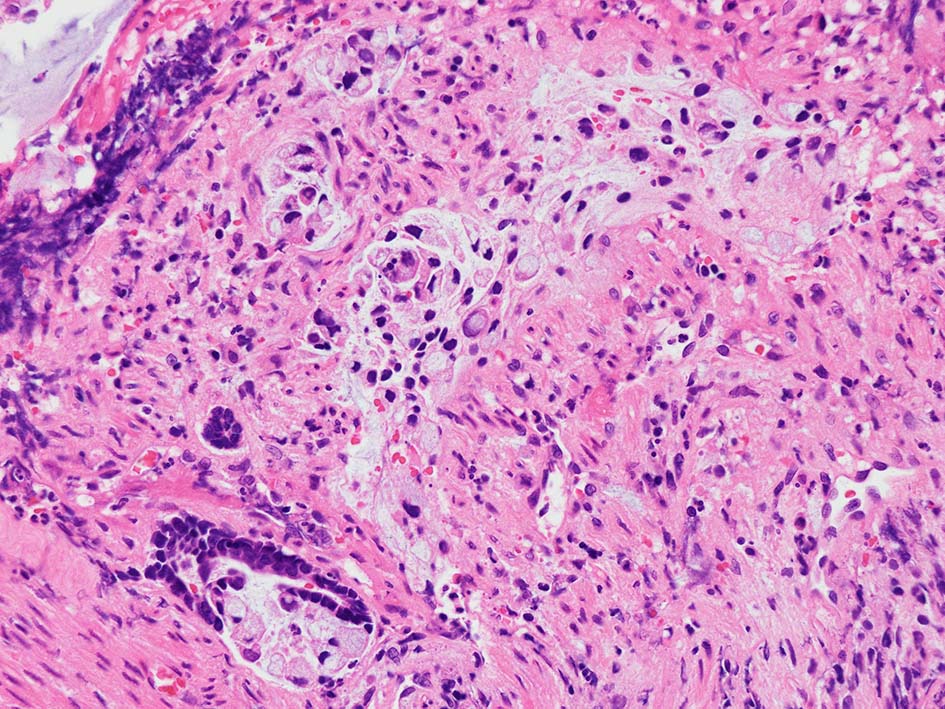

desmoplastic fibrosis, 粘液浸潤のみられる組織片にはsig, porのadenocarcinoma浸潤が確認される.

neutrophilic exudate の付着する腸管型腺癌部分. 核はより腫大し円形、vesicularとなっている. 上記腸管型とはCK20, CK7のそまりが異なっていた. 変性のためかもしれない.